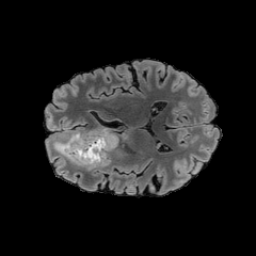

Tumour Information Preservation. For the brain tumor segmentation, we use a Swin UNETR model[27, 70], trained with random rotation, and intensity as data augmentation. In Figure 5, we highlight the tumor profiles of the generated MRIs compared to the ground truth tumour profile. In the test set with human ground-truth annotations (), the real MRI Dice score is 85.15 while the generated MRIs from a single slice have a dice score of 83.09. This shows how the generated MRIs indeed preserve the tumor information and can act as an affordable and informative pseudo-MRI, before conducting an actual costly MRI examination in hospitals.

B.4 Tumour Information Preservation

On the test set with human ground-truth annotations (), the brain volumes generated from single slice input preserve the volume of the different tumour components (paired t-test, for all 3 classes) (see Table 3). The real MRI Dice scores are put for reference to our generated MRIs. X-Diffusion outperforms baselines TPDM [36] and ScoreMRI [18] in tumour preservation (see Table 3 and Figure 12). We ran experiments comparing the tumour segmentation Dice Score varying X-Diffusion configurations. The multi-slice input X-Diffusion achieves a marginally better Dice Score than the single-slice input model (83.47 83.09). We also ran experiments with slice input used for volume reconstruction intersecting or not with tumour. We observe on average a drop of 6% Dice Score (see Table 3). Further away from the tumour the input slice for volume reconstruction is selected, and we observe a linear decrease in tumour segmentation Dice Score with the lowest value of 77.21 Dice Score (see Figure 15).

| Test Dice Score | |||||

|---|---|---|---|---|---|

| X-Diffusion Generated MRIs | ET | WT | TC | Average Dice | 3D PSNR(dB) |

| single slice | 75.48 | 89.24 | 84.57 | 83.09 | 35.81 |

| multi-slice | 75.82 | 89.56 | 85.04 | 83.47 | 36.13 |

| multi-slice (only-tumour) | 76.12 | 90.04 | 85.87 | 84.01 | 36.98 |

| multi-slice (no-tumour) | 70.14 | 84.29 | 81.65 | 78.69 | 33.24 |

| Real | 76.47 | 91.13 | 86.24 | 85.15 | N/A |